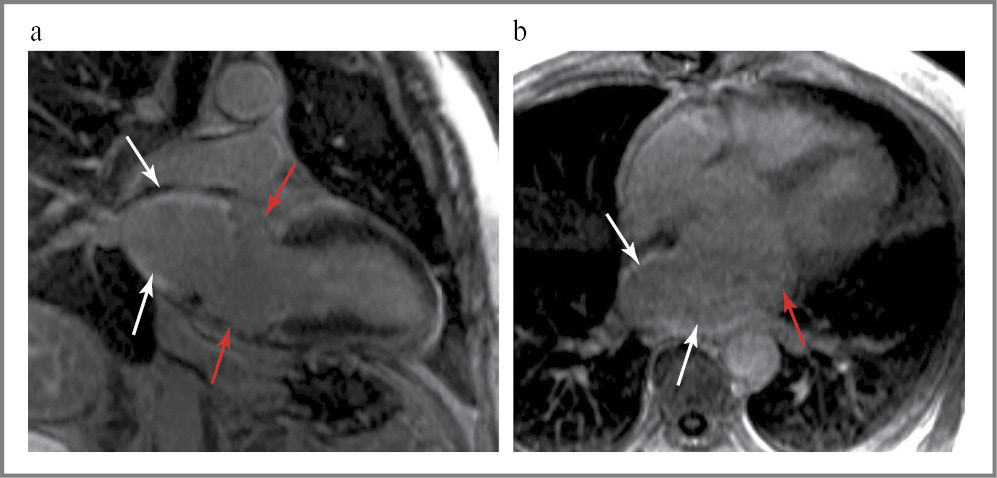

Проведена МРТ сердца с контрастированием. После введения контрастного препарата данных за его патологическое накопление миокардом желудочков не получено. Отмечается накопление контрастного препарата в утолщенной стенке верхних отделах ЛП (в остаточной части предсердия реципиента) в сравнении с частью предсердия (трансплантированной части) на уровне атриовентрикулярного кольца (рис. 5). Тромбы в камерах сердца не выявлены.

Рис. 5. МРТ сердца с контрастным усилением. Последовательность с отсроченным контрастированием: а – длинная ось сердца; b – четырехкамерная ось сердца. Белыми стрелками указано накопление контрастного препарата в верхних отделах ЛП (в остаточной части предсердия реципиента). Красными стрелками указано отсутствие накопление в миокарде ЛП нижних отделов на уровне атриовентрикулярного кольца (трансплантированной части).

Fig. 5. Contrast-enhanced cardiac MRI. Sequence with delayed contrast enhancement: a – long axis of the heart; b – four-chamber axis of the heart. The white arrows indicate the contrast agent uptake in the upper parts of the LA (in the residual part of the recipient’s atrium). The red arrows indicate the absence of uptake in the myocardium of the lower parts of the LA at the level of the atrioventricular ring (transplanted part).

Заключение: состояние после ортотопической трансплантации сердца от 2020 г. Деформация ЛП (постоперационные изменения), небольшое утолщение стенки ЛП в верхних отделах с накоплением контрастного препарата (в остаточной части предсердия реципиента). Накопление контрастного препарата в ЛП – неопределенного характера: с учетом клинико-лабораторных данных может соответствовать амилоидной инфильтрации, а также нельзя исключить накопление контраста в фиброзно измененном миокарде ЛП постоперационного генеза. Данных за очаговое поражение трансплантированных желудочков сердца не получено. Расширение ПП. Умеренное снижение сократимости миокарда ЛЖ. Расширение ветвей легочной артерии.